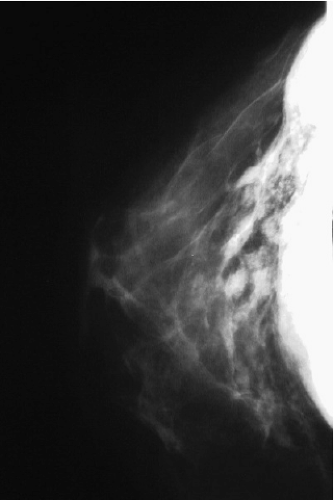

Routine mammographic screening of asymptomatic women facilitates early diagnosis of breast cancer. Over the years concerns have been raised about the accuracy of mammography in augmented patients (26,27). There are several ways implants may affect mammograms. The surgery can cause parenchymal scarring, resulting in architectural distortions, densities, or calcifications that appear on mammography. Implants (particularly when present over a prolonged period of time) compress breast tissue, increasing radiodensity, reducing contrast, and potentially interfering with identification of subtle lesions (28). The best-quality mammograms are obtained when the breast is maximally compressed so the x-ray beam penetrates the thinnest possible layer of tissue. With less compression, the volume of visualized tissue per unit area increases, causing more superimposition and potentially reducing mammographic sensitivity. Because implants are less compliant than breast tissue, they make it difficult to achieve the desired compression. During mammography the average nonaugmented breast can be compressed to a thickness of 4.5 cm, while the average augmented breast can be compressed only to a thickness of 7 cm (29).

The most important factor, affecting mammography in the augmented breast is the radiopaque shadow cast by the implant. Early reports estimated that only 25% of the breast is visualized after augmentation (30). Gumucio et al. (31) demonstrated that both saline and silicone implants can totally obscure early lesions such as microcalcifications. Hayes et al. (32) reported that 22% to 83% (38% on average) of the breast tissue could be obscured by the implant.

The extent to which an implant shadow interferes with mammography depends upon its size (33) and radiodensity (34). The density of the shadow is determined primarily by the physical and radiologic characteristics of the filler material. Both silicone and saline create a dense, radiopaque shadow that completely blocks visualization of adjacent breast tissue. Over the years several prostheses (e.g., Misti Gold implant, Trilucent implant) containing alternative filler materials have been introduced. However, none of these fillers proved entirely satisfactory and at the present time only saline- and silicone gel–filled implants are commercially available.

Our study revealed that in most patients there is a decrease in measurable breast tissue on postaugmentation films. The most important factor is capsular contracture: Little or no contracture (Baker 1 or 2) resulted in a 30% reduction in the area visualized, while moderate or severe contracture (Baker 3 or 4) resulted in a 50% reduction (Fig. 15-8). In patients who had serial mammography in the face of worsening contracture, there was progressive reduction in the amount of tissue visualized (Fig. 15-9). Implant position (submammary vs. submuscular) also proved important; on average, patients with submammary implants had a 37% reduction in area visualized, while patients with submuscular implants had only a 17% reduction.

In order to facilitate mammography in augmented women, Eklund et al. (35) developed the displacement or “push-back” technique (Fig. 15-10A,B), by which the implant is displaced posteriorly to allow a greater proportion of breast tissue to be captured on the mammogram. Using standard compression mammography, Eklund et al. determined that up to 97% of the breast tissue could be obscured by the implant, greatly increasing the likelihood of missing a significant lesion. The displacement technique led to an improvement in 99% of cases. Part of this improvement is likely attributable to the fact that implant displacement results in a compression advantage of up to 5 cm, leading to improved image quality and greater sensitivity. Subsequent studies confirmed the results of Eklund et al. in obtaining better visualization of breast tissue using implant displacement (36,37). Our study (38) also confirmed that slightly more tissue is visualized with displacement (average reduction of 25%) than with standard compression mammography (average decrease of 30%); however, with either technique there is a substantial reduction in area visualized compared to preaugmentation mammograms (Fig. 15-11).